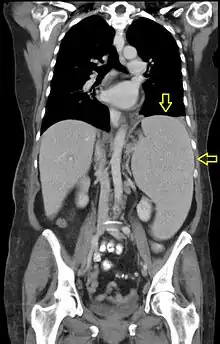

| CT scan in a patient with chronic lymphocytic leukemia, showing splenomegaly. Yellow arrows point at the spleen. | |

Abdominal CT is the most accurate. The spleen needs to be 2–3 times larger than normal to be palpable below the costal margin in physical examination.